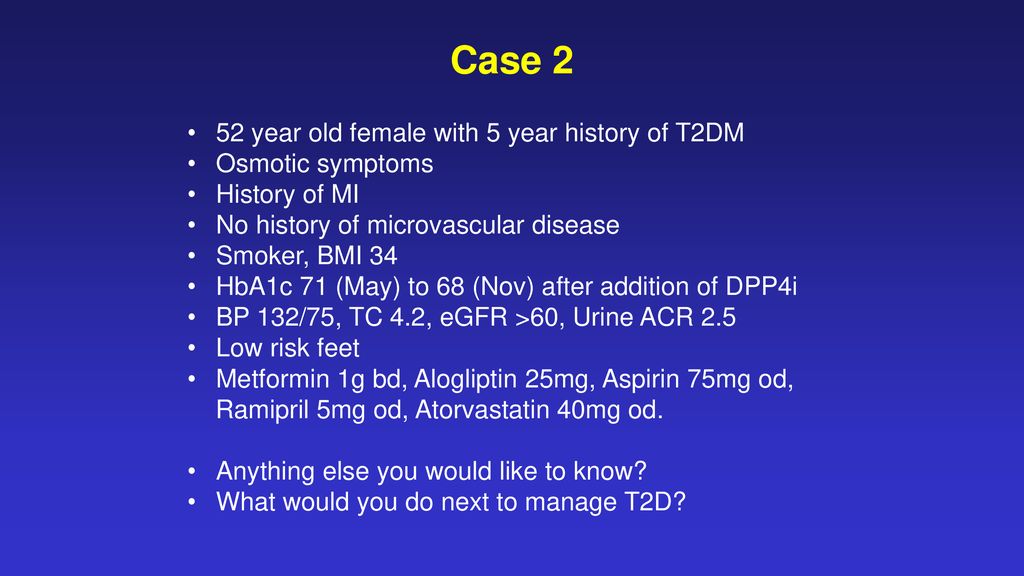

Priorities For Type 2 Diabetes Ppt Download